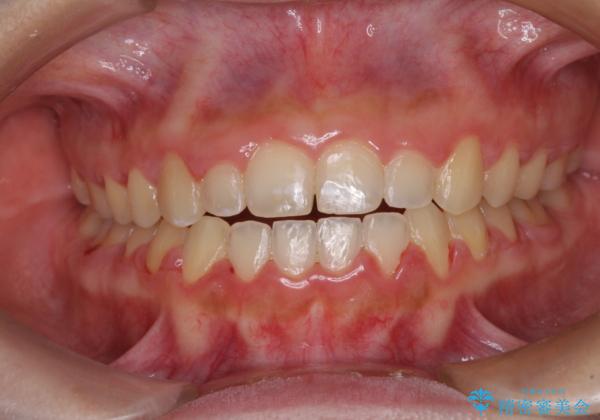

- 前歯のデコボコと、下顎の変位と受け口を気にして来院された患者様です。

初診時には大学病院にて顎の骨を切る外科矯正を勧めましたが、妥協的なゴールでも構わないので外科処置をせずに矯正を行いたいとのことでした。

まずは急速拡大装置にて上顎骨を側方に拡大し、インビザラインにて歯列と咬合を整えることとしました。

上顎骨を拡大したことで、下顎の歯列を上顎が受け入れられるようになりましたが、インビザラインでは咬み合わせを改善させることができなかったため、ワイヤー矯正にて仕上げることとしました。

ワイヤーを使用したものの、上下前歯のオープンバイトがなかなか改善されませんでしたが、患者希望により治療終了となりました。